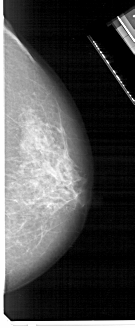

A_1706_1.RIGHT_MLO

RIGHT_MLO LINES 5176 PIXELS_PER_LINE 2671 BITS_PER_PIXEL 12 RESOLUTION 43.5 NON_OVERLAY